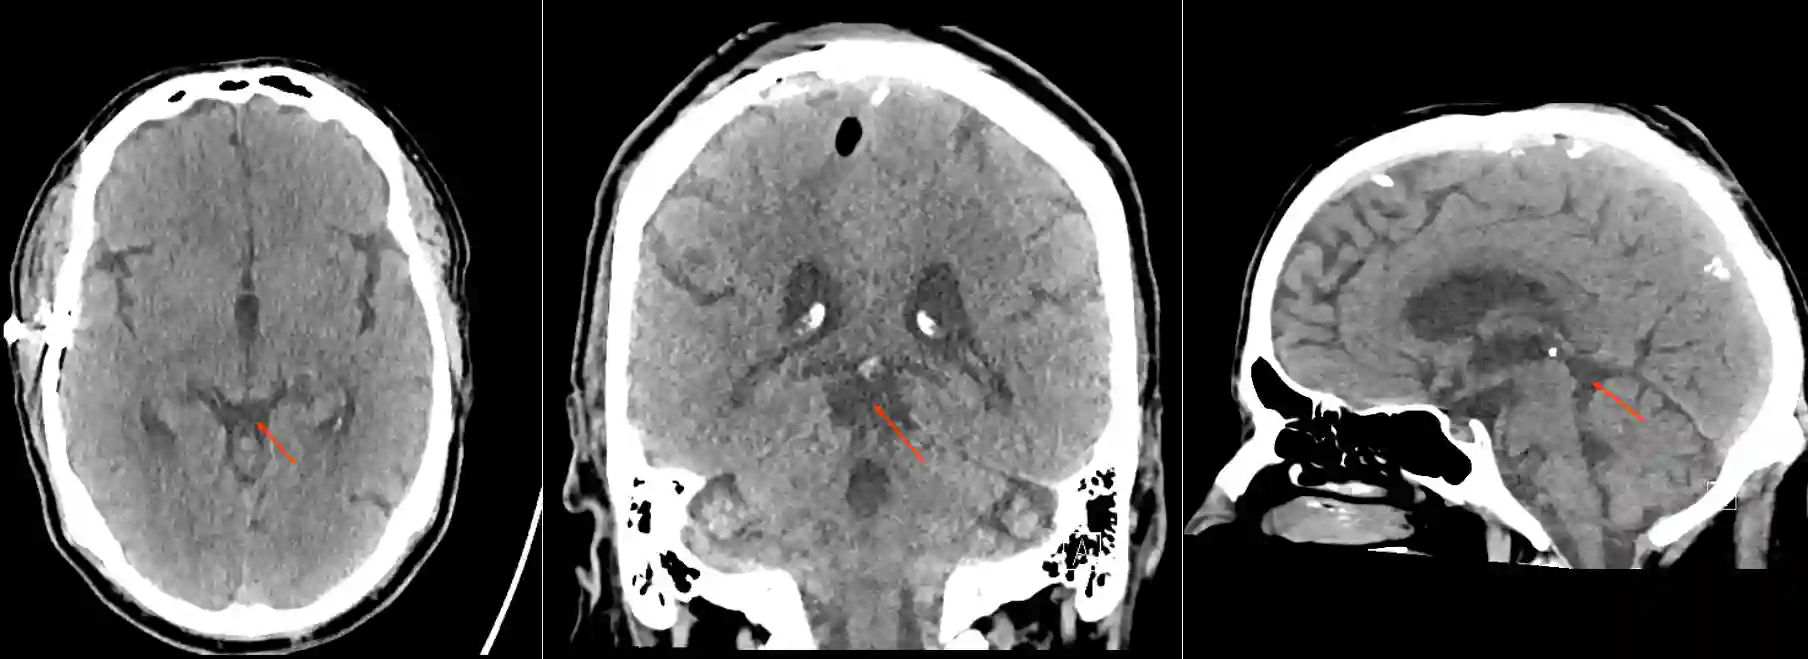

CT Cisterna quadrigeminalis

Darstellung der Cisterna quadrigeminalis in verschiedenen Ebenen im CT.